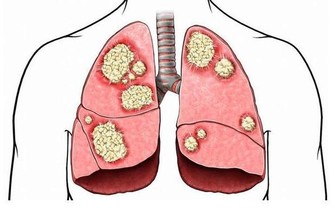

美國《PlosMedicine》雜誌刊載了一篇名為《酒精性臉紅的反應:來自於飲酒關於食管癌未知的風險因素》的論文,美國國家酗酒與酒精中毒研究所和日本久里濱酒精過敏研究中心的研究人員的聯合研究發現,對於體內缺乏乙醛脫氫酶2或這種酶不能正常發揮作用的人群來說,患食道癌的風險隨酒精攝入量的增多而增大。

這種風險發生的機率的可能遠遠大於那些飲酒後“面不改色”的人群。喝酒臉紅的人,其實是不能喝,請不要再逼他們了。